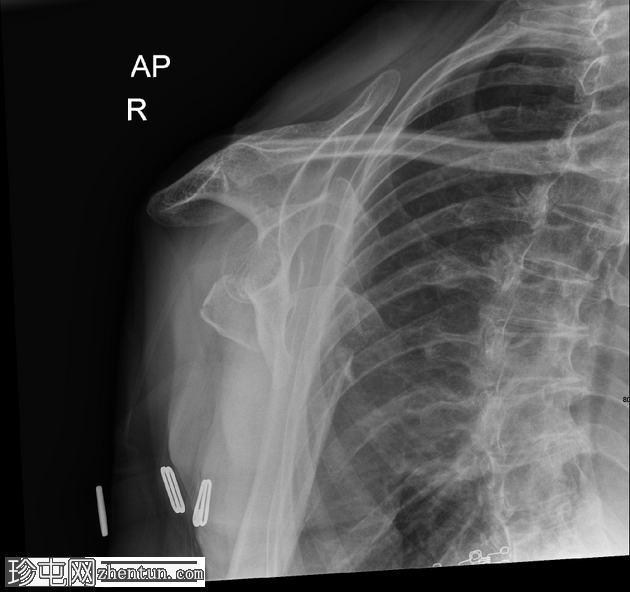

X线片

1.png

正位

右肱骨近端粉碎性骨折,严重移位,累及肱骨颈和肱骨大结节,伴肱骨近端相对于肩胛盂的前下脱位和肩关节脂肪血肿。肩锁关节完整;另可见胸椎侧弯、右侧颈部手术夹以及覆盖上臂和腋窝的衣物痕迹。

该X线片显示右肩高能量损伤,表现为肱骨近端粉碎性骨折,严重移位,累及肱骨颈和肱骨大结节。伴随的前下肩关节脱位反映了稳定软组织结构的破坏,这是此类骨折脱位模式的常见特征。脂肪血肿的存在表明骨折已延伸至关节内,骨髓脂肪渗入关节腔;这是评估损伤严重程度的重要影像学线索。